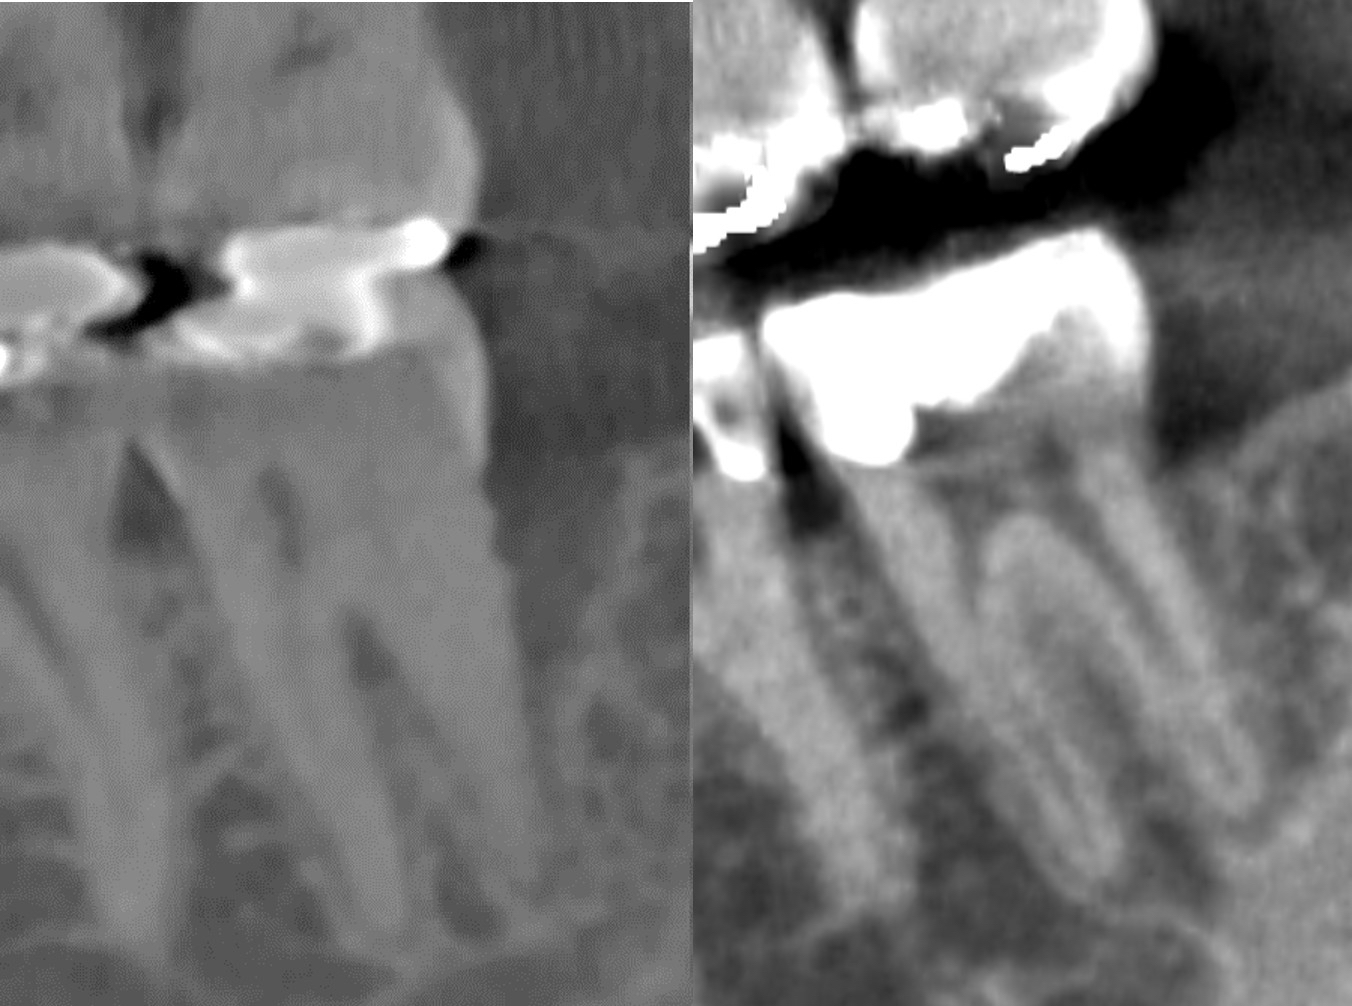

・CT画像で骨の再生を確認

下記画像は術式を説明しているシェーマ、再生療法後の骨の再生されたレントゲン像です。